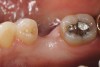

Figure 4a  Periodontally compromised mandibular incisors treatment planned for splinting with an adhesive fiber-reinforced composite resin.

Figure 4a

When fiber-reinforcing materials were introduced, the focus for their use was for periodontal splinting and stabilization resulting from tooth mobility.6,10,16,41-43 There is no doubt that splinting does reduce tooth mobility while the splint is in place.44 In the last decade, research supports the use of periodontal splinting as recommended therapy to stabilize those teeth to improve long-term prognosis.45-47 In a long-term clinical evaluation of splinting over a period of 48 to 96 months, using the original Ribbond Reinforcement Ribbon in fiber-reinforced composite resins was highly successful.17 The success of these splints can be attributed to close adaptation of the fiber ribbon to the tooth surface combined with cross stabilization of the mobile teeth by placing adhesive composite resin on the facial surfaces (Figure 4A through Figure 4E).34,35 Splinting of traumatized teeth with fiber-reinforcing materials and adhesive composite resin has also been reported.48,49 When using fiber to stabilize the traumatized tooth or teeth or for tooth stabilization after re-implantation, the tooth must be allowed to have some movement and not be fixed in place.50,51